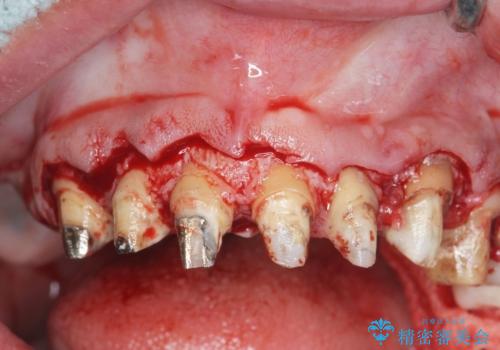

歯周外科を行い歯と歯槽骨・歯肉の関係を是正することで歯ぐきの状態を改善し、将来に亘り安定した歯周環境の維持を期待できるセラミック治療を実践します。

歯ぐきが腫れたままの状態だと、違和感が生じるとともに常に炎症が存在する環境となってしまうので非常に好ましくない口腔内環境です。